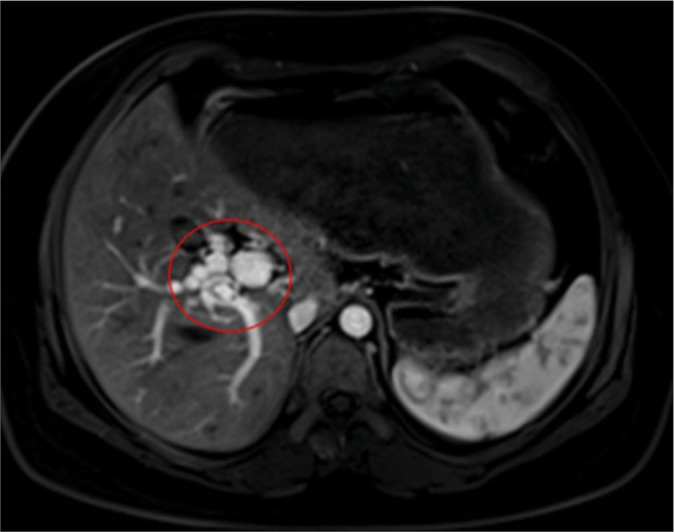

Portal vein (PV) anomalies are rare during embryonic development, with very few cases of duplicated PVs reported. This case reveals a new PV trunk anomaly, where computed tomography venography imaging shows three portal veins. The superior mesenteric vein and inferior mesenteric vein join to form a trunk that divides into two branches: One entering the liver (PV1) and the other ascending to join the splenic vein. The splenic vein then divides into two branches in the neck of the pancreas (PV2 and PV3), both entering the liver. The three PVs vary in thickness and all enter the liver through the first hepatic portal. Understanding the normal structure and anatomy of the PV is important for successful surgical planning. This case involves three main trunks of the PV, which is an extremely rare type of PV duplication anomaly. Reporting this case aims to enhance the awareness and understanding of PV duplication anomalies among clinicians and radiologists.